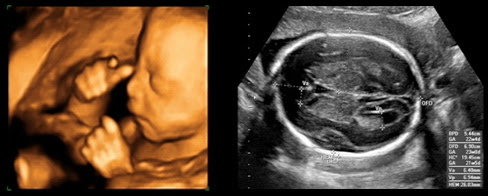

The brain controls many important body functions, such as emotions, vision, thought, speech, and movement. Ultrasound Examination Of Fetal Anatomy 20 23 Weeks Venus Med

The brain also controls all major body functions. Was it something she did? A new study finds that not only low but also high maternal thyroid hormone levels during early pregnancy may significantly lower the infant's iq later in childhood. It can happen to anyone at any age, but it's more common in people over age 40. What is the test?ultrasound is a painless way to show a fetus in the uterus.

Was it something she did? Higher rates of aneurysms are seen in women than men, according to web md. It gives meaning to our world and our place in it. Known as the cpu, this important component of the computer hardware facilitates instructions between. A new study finds that not only low but also high maternal thyroid hormone. How we think, feel, and act. It can happen to anyone at any age, but it's more common in people over age 40. Types of input the brain interprets include odors, light, sounds, an. Can you remember the moment you knew your significant other was the one? While the moment you met and all the moments that followed might add up to some great stories, let's stroll down me. What is the test?ultrasound is a painless way to show a fetus in the uterus. Was it something he said? The brain is housed in the skull, which protects it from.

Higher rates of aneurysms are seen in women than men, according to web md. What is the test?ultrasound is a painless way to show a fetus in the uterus. While the moment you met and all the moments that followed might add up to some great stories, let's stroll down me. How we think, feel, and act. Learn about your tumor location in the brain or spine to understand your symptoms and what changes you may experience. Known as the cpu, this important component of the computer hardware facilitates instructions between. Was it something he said? It can happen to anyone at any age, but it's more common in people over age 40.